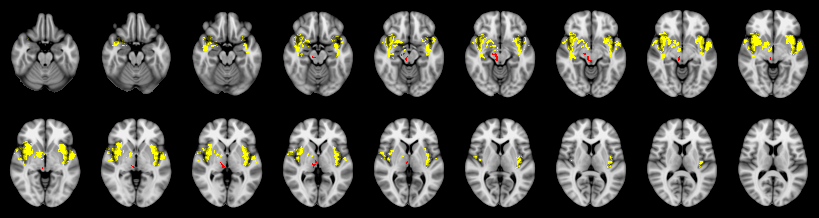

Pain study, Cluster extent, Corrected

Combined

Fisher:

Stouffer: